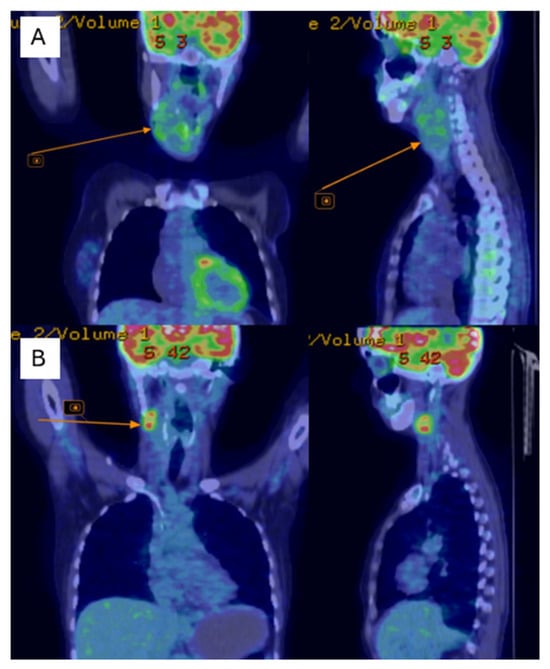

Postoperatively, the patient underwent adjuvant radiotherapy (total dose, 50 Gy in 25 fractions) to the left chest wall using a Halcyon linear accelerator, which was well-tolerated. Three months after radiotherapy, the patient developed dysphonia, and a subcutaneous tumor mass was observed in the right lateral cervical region. Cervical ultrasonography revealed immobile right lateral cervical lymphadenopathy measuring approximately 4 × 4 cm, with a normal-sized thyroid gland. Cervical magnetic resonance imaging (MRI) revealed a bilobed malignant tumor mass in the right laterocervical region, with invasion of the right thyroid cartilage and partial involvement of the right vocal cord. PET-CT showed metabolically active secondary lesions in the right lateral cervical lymph nodes and in the right lower pulmonary lobe (Figure 4A).

Figure 4.

PET-CT shows of the right jugular–carotid adenopathic mass (A)—before chemotherapy, (B)—after chemotherapy.

Follow-up cervical PET-CT (Figure 4B) and MRI (Figure 5A–C) showed a significant reduction in the size of the right jugular–carotid adenopathic mass, with residual lymphadenopathy and a favorable pulmonary response. No new metabolically active lesions were observed.

Figure 5.

Cervical region using MRI (A)—After chemotherapy (5 months post-surgery); (B,C)—after adjuvant chemotherapy; (D,E)—after adjuvant radiotherapy; (F,G)—After first round of palliative chemotherapy; (H,I)—after second round of palliative chemotherapy.

Subsequently, the patient underwent re-irradiation (60 Gy in 30 fractions to the right laterocervical lymph nodes and 50 Gy in 25 fractions to the left laterocervical lymph nodes). Despite treatment, cervical MRI revealed rapid progression of metastatic disease, with marked enlargement of adenopathy infiltrating the thyroid cartilage, partially encasing the trachea, and thyroid lobes (Figure 5D–G). Palliative chemotherapy with gemcitabine and docetaxel was recommended for the patient.

At 15 months of follow-up, the patient developed progressive left lateral cervical swelling associated with worsening dyspnea. Cervical computed tomography revealed a large, multilobulated proliferative mass located in the anterior and left lateral cervical regions, containing non-critical internal necrotic areas, with significant narrowing and rightward displacement of the trachea. Additionally, a right submandibular lymph node measuring 1.6 cm with a necrotic center was observed. Chest computed tomography revealed a metastatic lesion measuring 3.0 × 2.8 cm in the lower lobe of the right lung (Figure 5H,I).